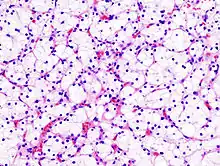

| Micrograph of the most common type of renal cell carcinoma (clear cell)—on right of the image; non-tumour kidney is on the left of the image. Nephrectomy specimen. H&E stain | |

Clear Cell Renal Cell Carcinoma (CCRCC) ![]() Generally the cells have a clear cytoplasm, are surrounded by a distinct cell membrane and contain round and uniform nuclei. |

The gross and microscopic appearance of renal cell carcinomas is highly variable. The renal cell carcinoma may present reddened areas where blood vessels have bled, and cysts containing watery fluids.[58] The body of the tumour shows large blood vessels that have walls composed of cancerous cells. Gross examination often shows a yellowish, multilobulated tumor in the renal cortex, which frequently contains zones of necrosis, haemorrhage and scarring. In a microscopic context, there are four major histologic subtypes of renal cell cancer: clear cell (conventional RCC, 75%), papillary (15%), chromophobic (5%), and collecting duct (2%). Sarcomatoid changes (morphology and patterns of IHC that mimic sarcoma, spindle cells) can be observed within any RCC subtype and are associated with more aggressive clinical course and worse prognosis. Under light microscopy, these tumour cells can exhibit papillae, tubules or nests, and are quite large, atypical, and polygonal.

Recent studies have brought attention to the close association of the type of cancerous cells to the aggressiveness of the condition. Some studies suggest that these cancerous cells accumulate glycogen and lipids, their cytoplasm appear "clear", the nuclei remain in the middle of the cells, and the cellular membrane is evident.[59] Some cells may be smaller, with eosinophilic cytoplasm, resembling normal tubular cells. The stroma is reduced, but well vascularised. The tumour compresses the surrounding parenchyma, producing a pseudocapsule.[60]

The most common cell type exhibited by renal cell carcinoma is the clear cell, which is named by the dissolving of the cells' high lipid content in the cytoplasm. The clear cells are thought to be the least likely to spread and usually respond more favourably to treatment. However, most of the tumours contain a mixture of cells. The most aggressive stage of renal cancer is believed to be the one in which the tumour is mixed, containing both clear and granular cells.[61]